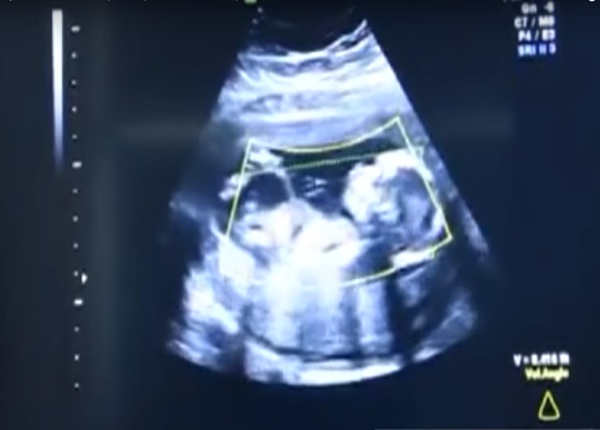

Após um ultrassom, os médicos ficaram chocados ao descobrir que o bebê não estava no útero, mas sim no abdômen da mãe.

“Provavelmente, o bebê foi concebido normalmente, mas o óvulo acabou sendo implantado em um lugar atípico.

O bebê estava crescendo fora do útero”, explicou o médico cirurgião Vladimir Borovkov, responsável pelo Centro Pré-natal Regional de Altai.